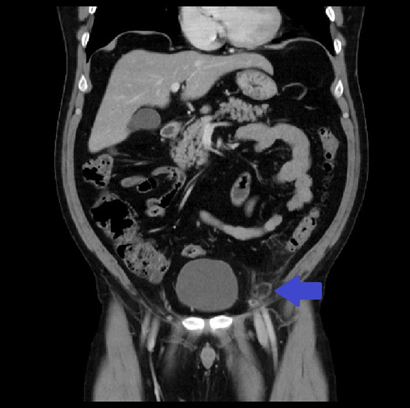

A 56-year-old man presented to the emergency department with a one week history of abdominal pain in the left lower quadrant with irradiation to the same side lumbar area. On the physical abdominal examination, he had localised tenderness in the left iliac fossa. Laboratory results showed white blood cell (WBC) count of 9.12 10e3/µL (4.00 - 12.00) and a C reactive protein (CRP) of 14.2 (<=5). A computed tomography (CT) scan was performed, which informed findings suggestive of epiploic appendagitis and multiple diverticula in the sigmoid colon (Figures 1, 2). The patient was sent home with conservative treatment.

Figure 1 Inflammatory appearance changes at the level of the epiploic appendage adjacent to the sigmoid colon. Axial plane.